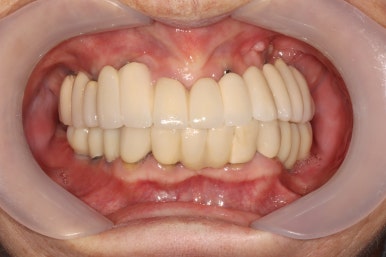

생각보다 임시치아보다 훨씬 매끈한 표면과 비슷한 색깔을 자랑하는 지르코니아 크라운입니다.

아마 어금니에 임플란트가 생긴건가? 싶으실거에요.

오스템 원가이드 네비게이션 임플란트 시스템을 이용하면, 정교하게 이상적인 위치에 임플란트를 심어낼 수 있어 자연스러운 임플란트 보철물을 제작하는데 많은 도움을 받을 수 있습니다!!

최종 완성된 보철물은 상당히 이상적인 형태를 갖고 있습니다.

이제 드디어 부분틀니를 쓰지 않아도 되는 ... 행복한 순간입니다.

차이를 별로 못느끼실 수 있겠지만, 임플란트 보철물 완성 6개월 후 방문 때 구강내 사진입니다.

감사히도 환자분께서 상당히 깨끗하게 유지하고 계셔서, 잇몸에 염증하나 없이 너~무 보기 좋더라구요.